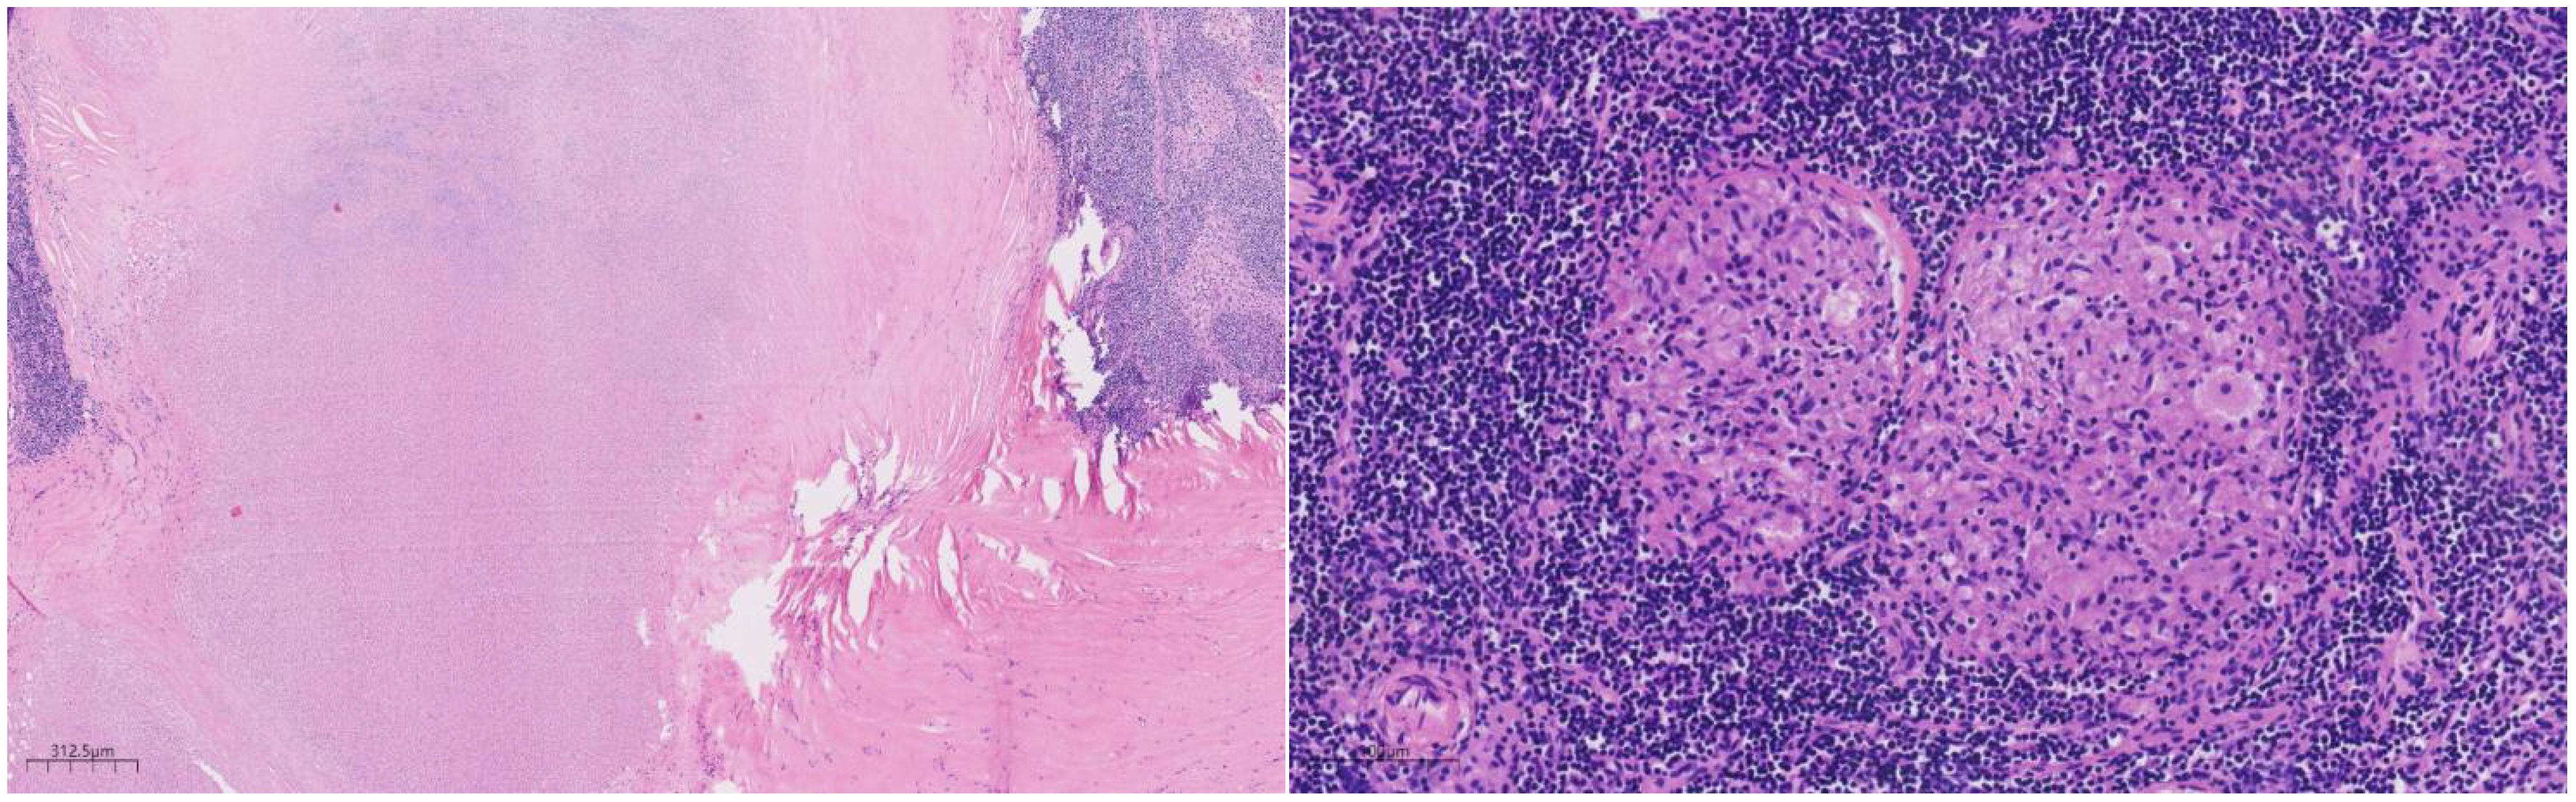

Histologically (Figures 24), the benign intraductal papilloma exhibited a papillary structure comprising two cellular layers: an inner epithelial layer and an outer basal myoepithelial layer, the latter extending continuously along the papillary axis and duct wall (Figures 2-4). The lesion contained low-grade DCIS, which demonstrated a papillary structure with solid or window-like formations. Nuclei were predominantly arranged in a polar orientation, slightly enlarged, oval to round in shape, uniform in size, and without overlap. Nuclear membranes were smooth, chromatin appeared uniform, varying from dusty to finely granular, and nucleoli were inconspicuous, with mitotic figures rarely seen. Notable areas of necrosis were observed in the axillary lymph nodes, surrounded by fibrous tissue or granulomas (Figure 5).

Figure 2

Histological image showing a cross-section of tissue stained with hematoxylin and eosin. The section reveals densely packed cells and fibrous structures in varying shades of purple and pink, indicating different tissue components. A scale bar at the bottom left measures six hundred twenty-five micrometers.

Figure 2. Low magnification shows papillary hyperplasia in the breast duct with clear margins. H&E ×15.7.